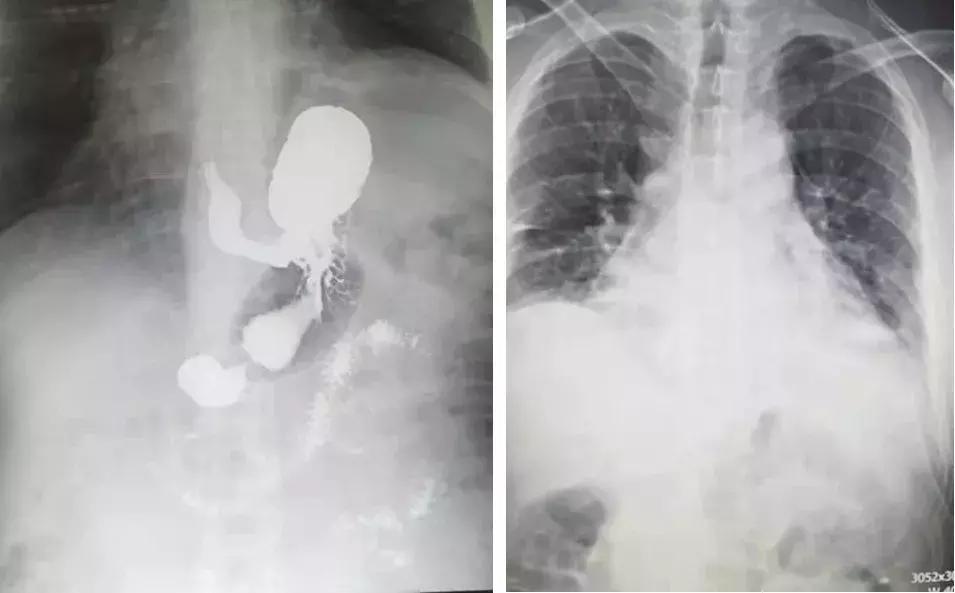

患者郭某,男,42岁,一家奶牛场工人。2月27日,患者在给奶牛喂料时,被奶牛挤压左侧胸部,伤后患者胸痛,伴轻度胸闷、气短。伤后第3天在西安某医院行胸部CT检查提示(见下图左):1. 左侧膈肌明显膨升伴左肺下叶膨胀不良;2. 左侧第6肋骨骨折。3月2日到我院胸外科门诊就诊。潘龙毅主任医师接诊后诊断为左侧膈肌明显膨升伴左肺下叶膨胀不良。认为患者应该手术将抬高的膈肌复位,促使肺膨胀,否则,日后患者胸闷、气短会加重。3月4日,患者住院行肺功能检查果然提示:中重度限制性肺通气功能障碍。住院确诊为:1.左侧膈肌显著膨升伴左肺膨胀不良;2. 左侧第6肋骨骨折。在心胸外科徐涛主任的胸外科同仁支持下,于2019年3月7日下午2时由潘龙毅主任医师主刀王鑫副主任医师协助在全麻行左侧膈肌折叠术,手术顺利,历时2小时。术后第2天复查胸片见左侧膈肌完全复位,左肺完全复张,疗效显著(见下图右)。在白娟护士长带领的心胸外科护士团队的精心护理下。现患者已完全康复出院。